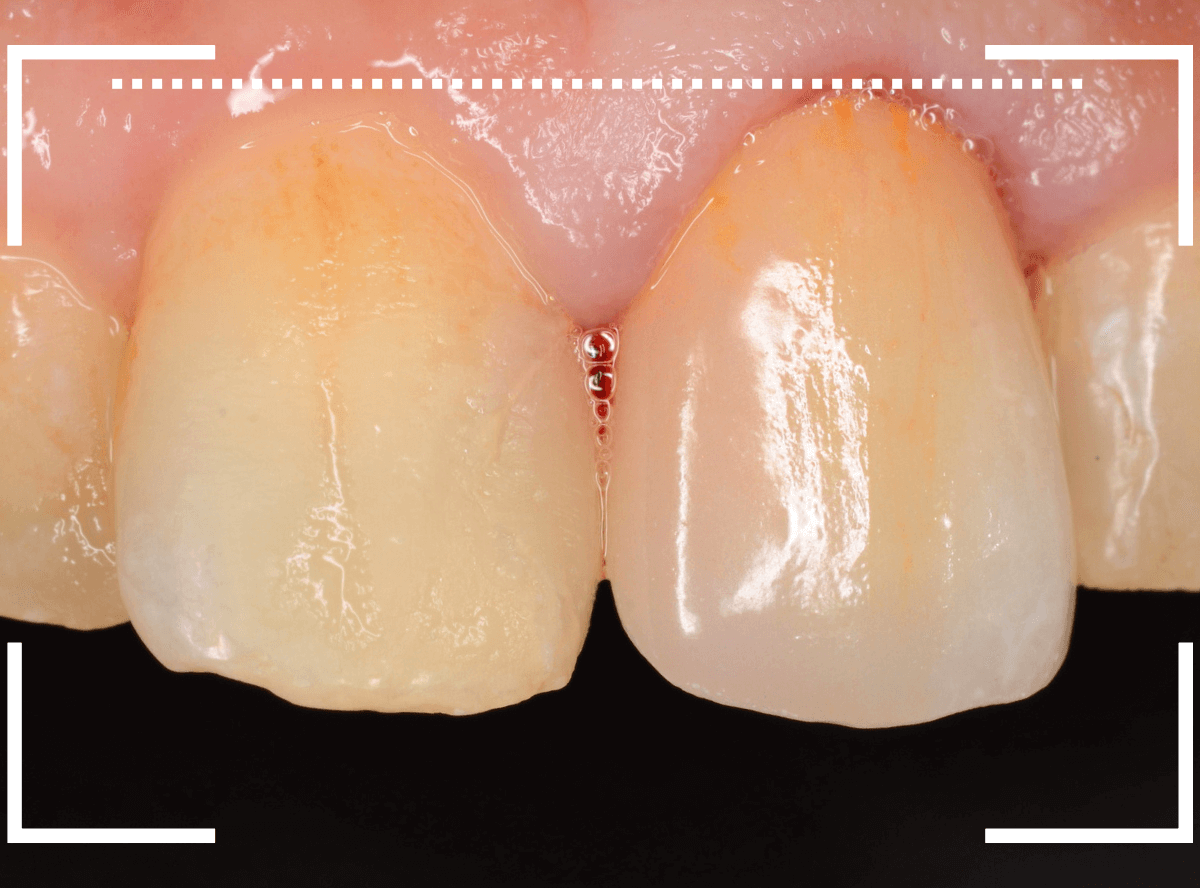

Case.16 保険のさし歯(レジン前装冠)をジルコニア・セラミックへ

以前に治療した上のさし歯を綺麗にやり直したいというご相談の患者さんです。

保険診療で行うさし歯「レジン前装冠」が入っています。

「レジン前装冠」は裏から撮影した写真を見ていただければわかるように、銀歯の上にレジン(プラスチック)を盛ったさし歯で、実質的には銀歯です。

銀歯の上にプラスチックを盛るために、歯をかなり大きく削る必要があったり、短期間で劣化・変色する(この方の差し歯も劣化してのっぺりした黄土色になっています)、金属の色素が歯肉に溶け出して歯肉が黒くなる(メタル・タトゥー)などのデメリットがあります。